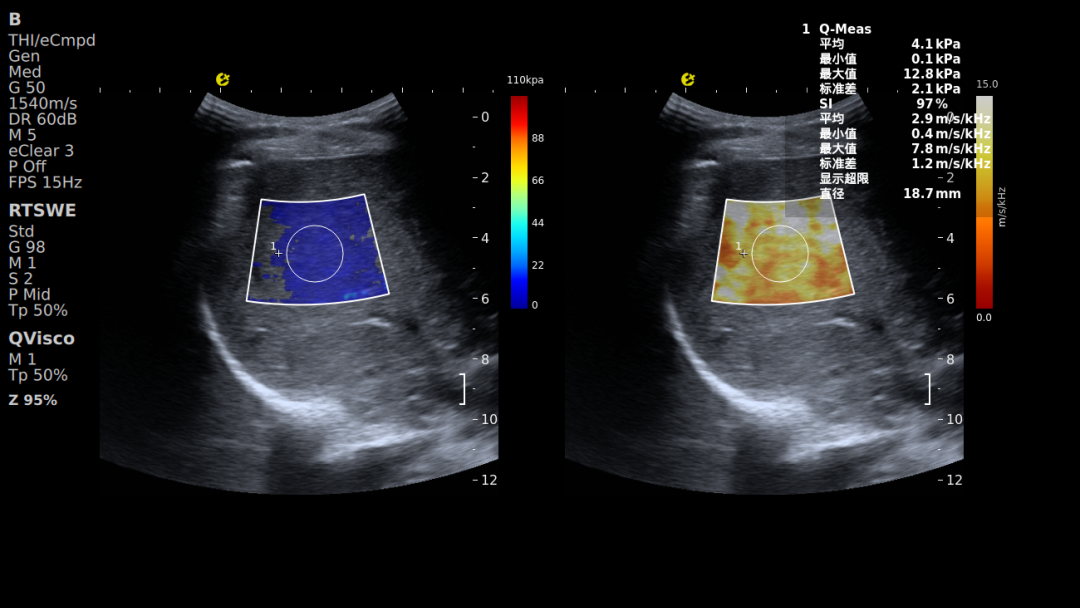

黏弹性定量成像-QVisco™

可精准揭示肝脏组织微观病理改变,清晰呈现肝脏从“可逆功能异常”到“不可逆结构改变”的整个病理过程。该参数能够评估细胞水肿、炎症浸润及脂质堆积等细微变化,有效弥补了传统弹性技术对微观病变与炎症活动识别能力的不足,为肝脏病理分层提供了新的影像维度,已被多项临床研究证实其应用价值。